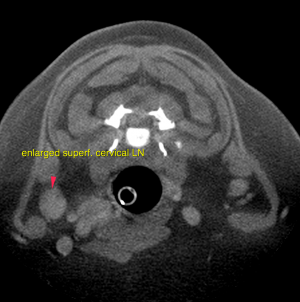

A well-defined, ovoid mass lesion with lobulated appearance and undulating surface is seen in the area of the right parotid salivary gland, measuring 3.8 x 3 x 3.5 cm in size. After contrast administration the mass lesion presents moderate irregular contrast enhancement with multiple spherical non-contrast enhancing areas. The right superficial cervical lymph node is prominent and presents a moderate increased short-to-long-axis ratio of 0.5. The right thyroid gland presents severe enlargement at 2.4 x 2.4 x 2.8 cm. The regular parenchyma is completely displaced by ill-defined moderately contrast enhancing tissue with multiple spherical non-contrast enhancing areas. At the level of the neck the tracheal rings are mildly flattened and the luminal diameter is reduced.

Differential diagnosis for the salivary gland mass includes primary soft tissue neoplasia (fibrosarcoma) with invasion of the parotid salivary gland or – even though rare in canine – primary neoplasia of the parotid salivary gland (such as adenocarcinoma or less likely adenoma).For further workup – if not performed yet – FNA samples or biopsy are essential. Surgical excision is advised. The right thyroid gland presents a mass lesion compatible with primary neoplasia. Possible differential diagnosis are cystic adenocarcinoma or less likely adenoma. In dogs these are rarely functional. Surgical removal of the right thyroid is the therapy of choice. FNA samples from the right superficial cervical lymph node are essential prior to surgery for complete staging. The findings of the right adrenal gland are consistent with primary neoplasia. Possible differentials include functional/non-functional adenoma or adenocarcinoma, pheochromocytoma. Invasion of the phrenicoabdominal vein is likely, invasion of the caudal vena cava cannot be ruled out. The potential of vascular invasion increases the odds of a primary malignancy.